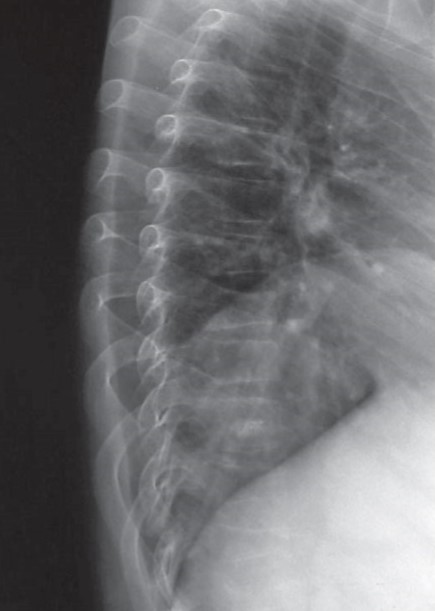

GCs toxicity appears to have a predilection for trabecular bone, which has a higher metabolic activity than cortical bone, and thus may be more sensitive to the deleterious effect of steroids [35]. This is supported by the propensity of GCs to affect the spine (fig. 1).

Figure 1. Vertebral compression following 5 years’ deflazacort use, given to retard deterioration in muscle strength in a 13-year-old patient with Duchenne’s muscular dystrophy.

Studies in adults have shown that the magnitude of the GC effect on bone appears to be dose dependent [9]. However, it remains unsettled whether low doses cause bone loss in all patients. The concept of a threshold dose is controversial in the adult field, as even low doses of GCs affect skeletal metabolism [48]. In adults with rheumatoid arthritis, it appears from a clinical perspective that a dose of prednisone <5 mg/day is relatively safe [49, 50]. Alternate day steroid use does not appear to reduce the skeletal effect compared to daily administration, at higher doses [51]. The lowest-dose threshold for children, if it exists, has not been determined. Deflazacort, an oral steroid derivative, has a bone-sparing effect when compared to prednisone or methylprednisone in the short term [52, 53] [ However, a report of 46 boys with Duchenne’s muscular dystrophy who received deflazacort over a 4-year period showed that 26/46 (52%) of the boys suffered 37 fracture events [54]. Of the 37 fractures, 39% were vertebral compression fractures, while the rest were long bone fractures. Significant decrements in bone mass were also observed over the study period in these boys who were on deflazacort. Among boys with Duchenne’s who did not receive steroids, Larson and Henderson [55] observed that 44% of patients had sustained fractures, the majority ofwhich occurred in the lower extremities. None of these patients were noted to have vertebral compression. These results suggest that the osteotoxic effect of deflazacort appears to exacerbate the underlying predisposition for osteoporosis in boys with Duchenne’s muscular dystrophy, and has a predilection for the spine. Inhaled GCs have fewer systemic, including skeletal, effects compared to oral or intravenous therapy [56-58], unless they are administered at high doses [59, 60].